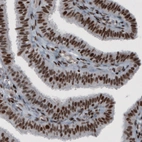

Immunohistochemical staining of human fallopian tube shows strong nuclear immunoreactivity in glandular and connective tissue cells.